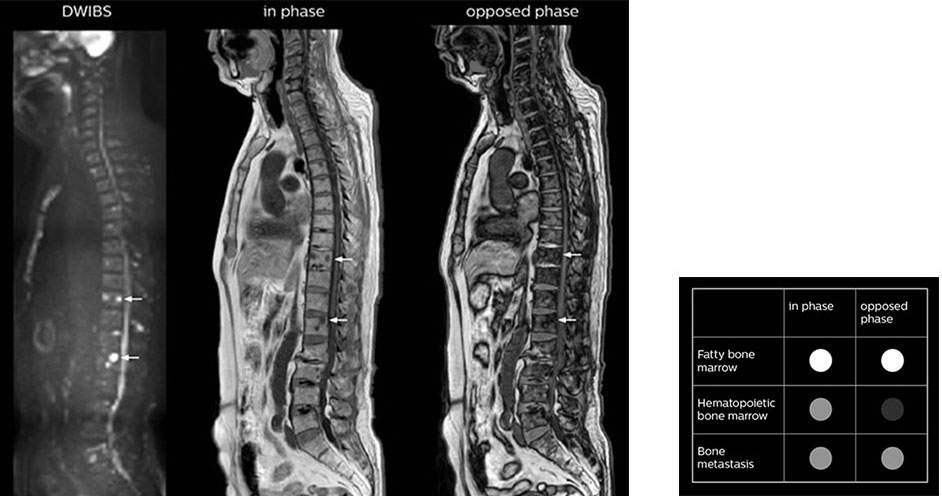

“In-phase and out-phase sagittal T1-weighted FFE images help us to visualize and further characterize bone lesions such as metastasis and bone-marrow hyperplasia that have high signal on DWI. These images are also used throughout radiotherapy, to monitor changes in the fatty bone marrow.”

“mDIXON FFE allows us to quickly get information we need to assess the presence of fat. That gives us more information when we need to diagnose bone lesions, and when we are asked to judge fat-containing lesions such as hepatocellular or renal carcinoma,” Dr. Nobusawa says. “The mDIXON fat images can help us to differentiate fatty bone marrow from bone lesions. This is especially useful in elderly people, who tend to have fattier bone marrow. The water images provide a high signal-to-noise ratio in the intestinal canal, which is valuable for visualizing lesions in the colon,” he says.